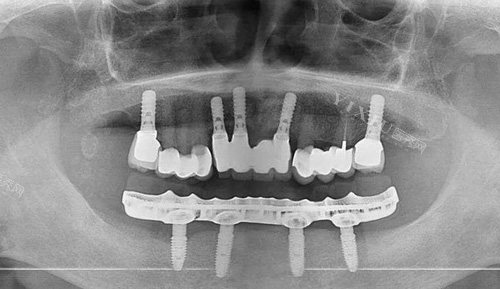

数字种植牙通过CBCT扫描、口内光学扫描获取三维口腔数据,生成虚拟模型后进行术前规划,并利用3D打印导板引导种植体植入。传统种植牙则依赖医生经验,通过物理模型和X光片判断种植位置,依赖手工操作完成植入。

通过智能化软件模拟种植体位置、方向和深度,避开血管、神经等重要结构,优化骨量利用。

3D打印导板辅助医生精细植入种植体,误差控制在毫米级,适合复杂骨条件或高龄患者。

通过石膏模型和X光片评估口腔状况,依赖医生对解剖结构的理解。

适用于牙槽骨萎缩、骨质疏松患者,通过特殊力学设计减少种植体数量。

需配备CBCT、口扫仪、3D打印机等设备,成本较高。